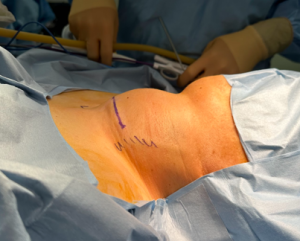

수술은 근전도 튜브를 이용하여 진행하였고, 환자분의 의사소통 및 협조가 쉽지 않을 수 있는 점 고려하여 기관절개술을 시행한 뒤 수술을 종료했습니다.

CT에서 보이는 모양은 암처럼 보이지는 않았지만, 뭔가 모종의 병리가 있을 것으로 판단은 되었으나 야간 응급수술이었던 탓이 동결절편검사를 하지 못하고, 안전한 회복을 위해 기관절개술을 진행하고 수술을 마쳤습니다.